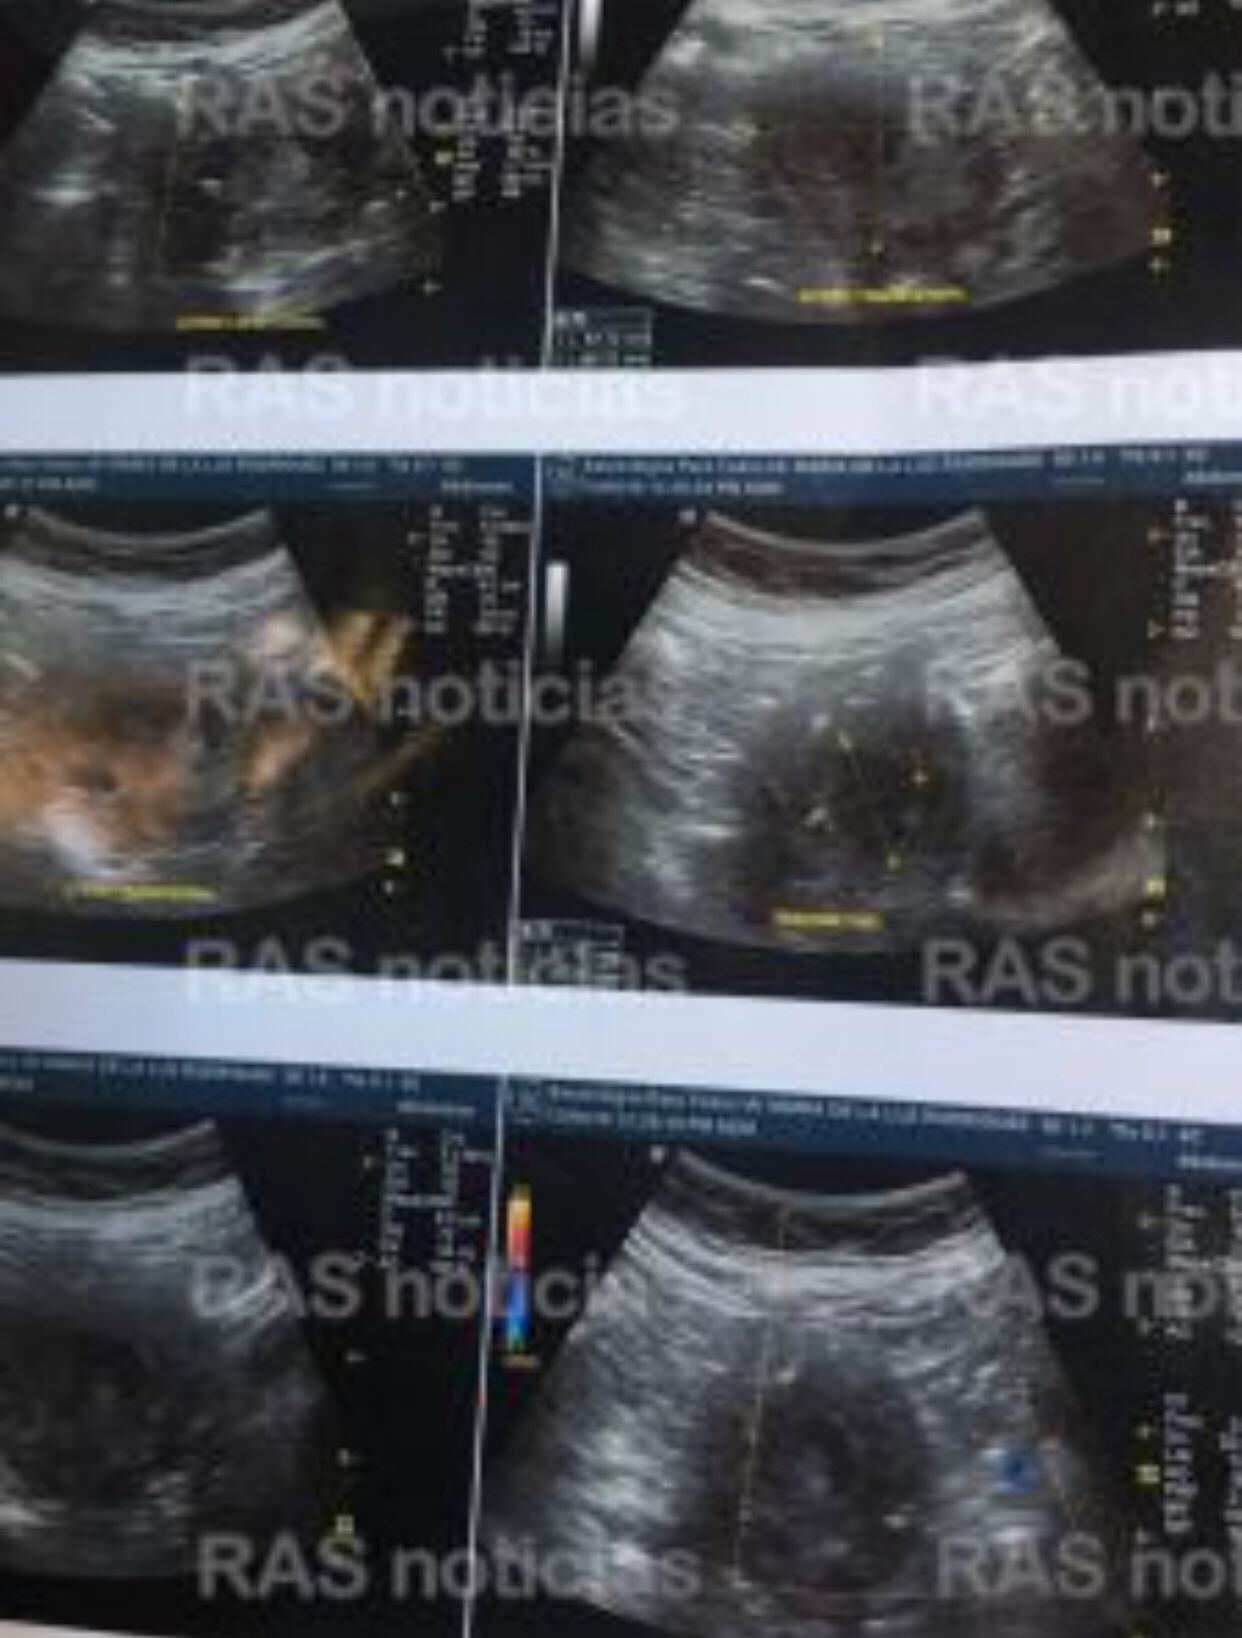

Ella pensaba que sería uno solo, pues ahí se vería que era lo que tenía. Solo que los encargados no podían dar crédito al resultado de la imagen y le hicieron ocho placas más, para que no quedada ninguna duda.